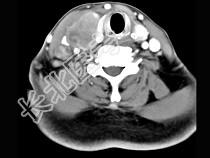

- 多项选择题女性,54岁, 右侧颈部肿大近1年,近来病人有声嘶、吞咽困难, CT扫描如图,请选择正确的描述和答案 ( )

A、右侧甲状腺肿大,密度减低

B、增强扫描示甲状腺呈不规则强化团块影,其内有低密度区,病灶境界不清

C、右侧颈内静脉增粗,其内可见不规则充盈缺损区

D、考虑甲状腺癌

E、右侧颈内静脉瘤栓形成